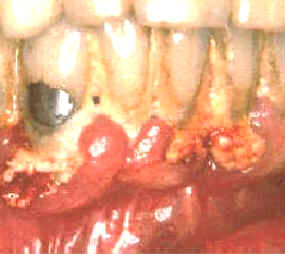

| Estas imágenes muestran inmediatamente como queda luego

de la limpieza con instrumental ultrasónico.

La gingiva se desprende del diente y la mayoría del epitelio de la

bolsa periodontal queda expuesto. El sangrado durante el tratamiento es intenso y el paciente

suele notar algún sangrado post operatorio de la encía. Los tejidos

blandos suelen molestar. |

| Durante algunos días el paciente al comer y

cepillar sus dientes, puede presentar síntomas de dolor y sangrado.

Suele ocurrir bacteremia

durante el tratamiento y durante algunos días posteriores debido

al cepillado dental. El tejido conjuntivo expuesto y el epitelio frágil

permiten el pasaje de las bacterias orales a los vasos sanguíneos.

Deben administrarse antibióticos en

forma profiláctica en los

pacientes que

presentan condiciones sistémicas riesgosas si ocurriera una bacteremia. |